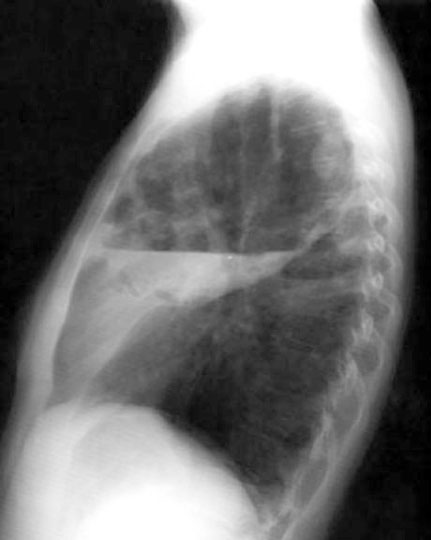

Case 12 Labeled Image

Labeled Image

Follow the progression of break down of tumor. What are stalactites and stalagmites?